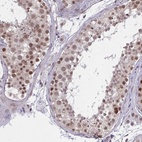

Immunohistochemical staining of human testis shows strong nuclear positivity in cells in seminiferus ducts.